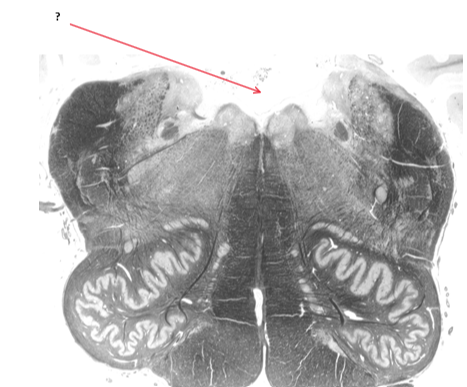

Name this and state its function.

Inferior cerebellar peduncle.

Name this and state its function.[5 marks overall].

Tract involved.

Pathway specific to function.

Medial lemniscus.

Name this.

Fourth ventricle.